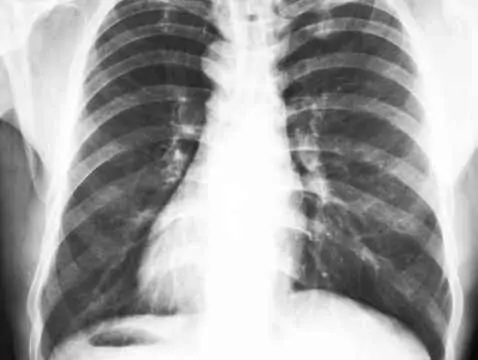

Para diagnosticar las enfermedades cardiovasculares, especialmente los defectos cardíacos, que constituyen el mayor problema en cardiología, se recurre a una historia clínica bien elaborada, una...